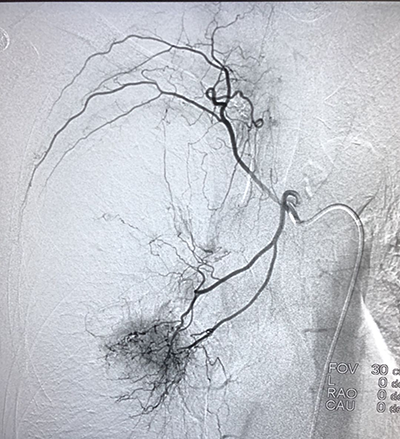

(肺癌的介入治療)(盆腔惡性腫瘤的介入治療)